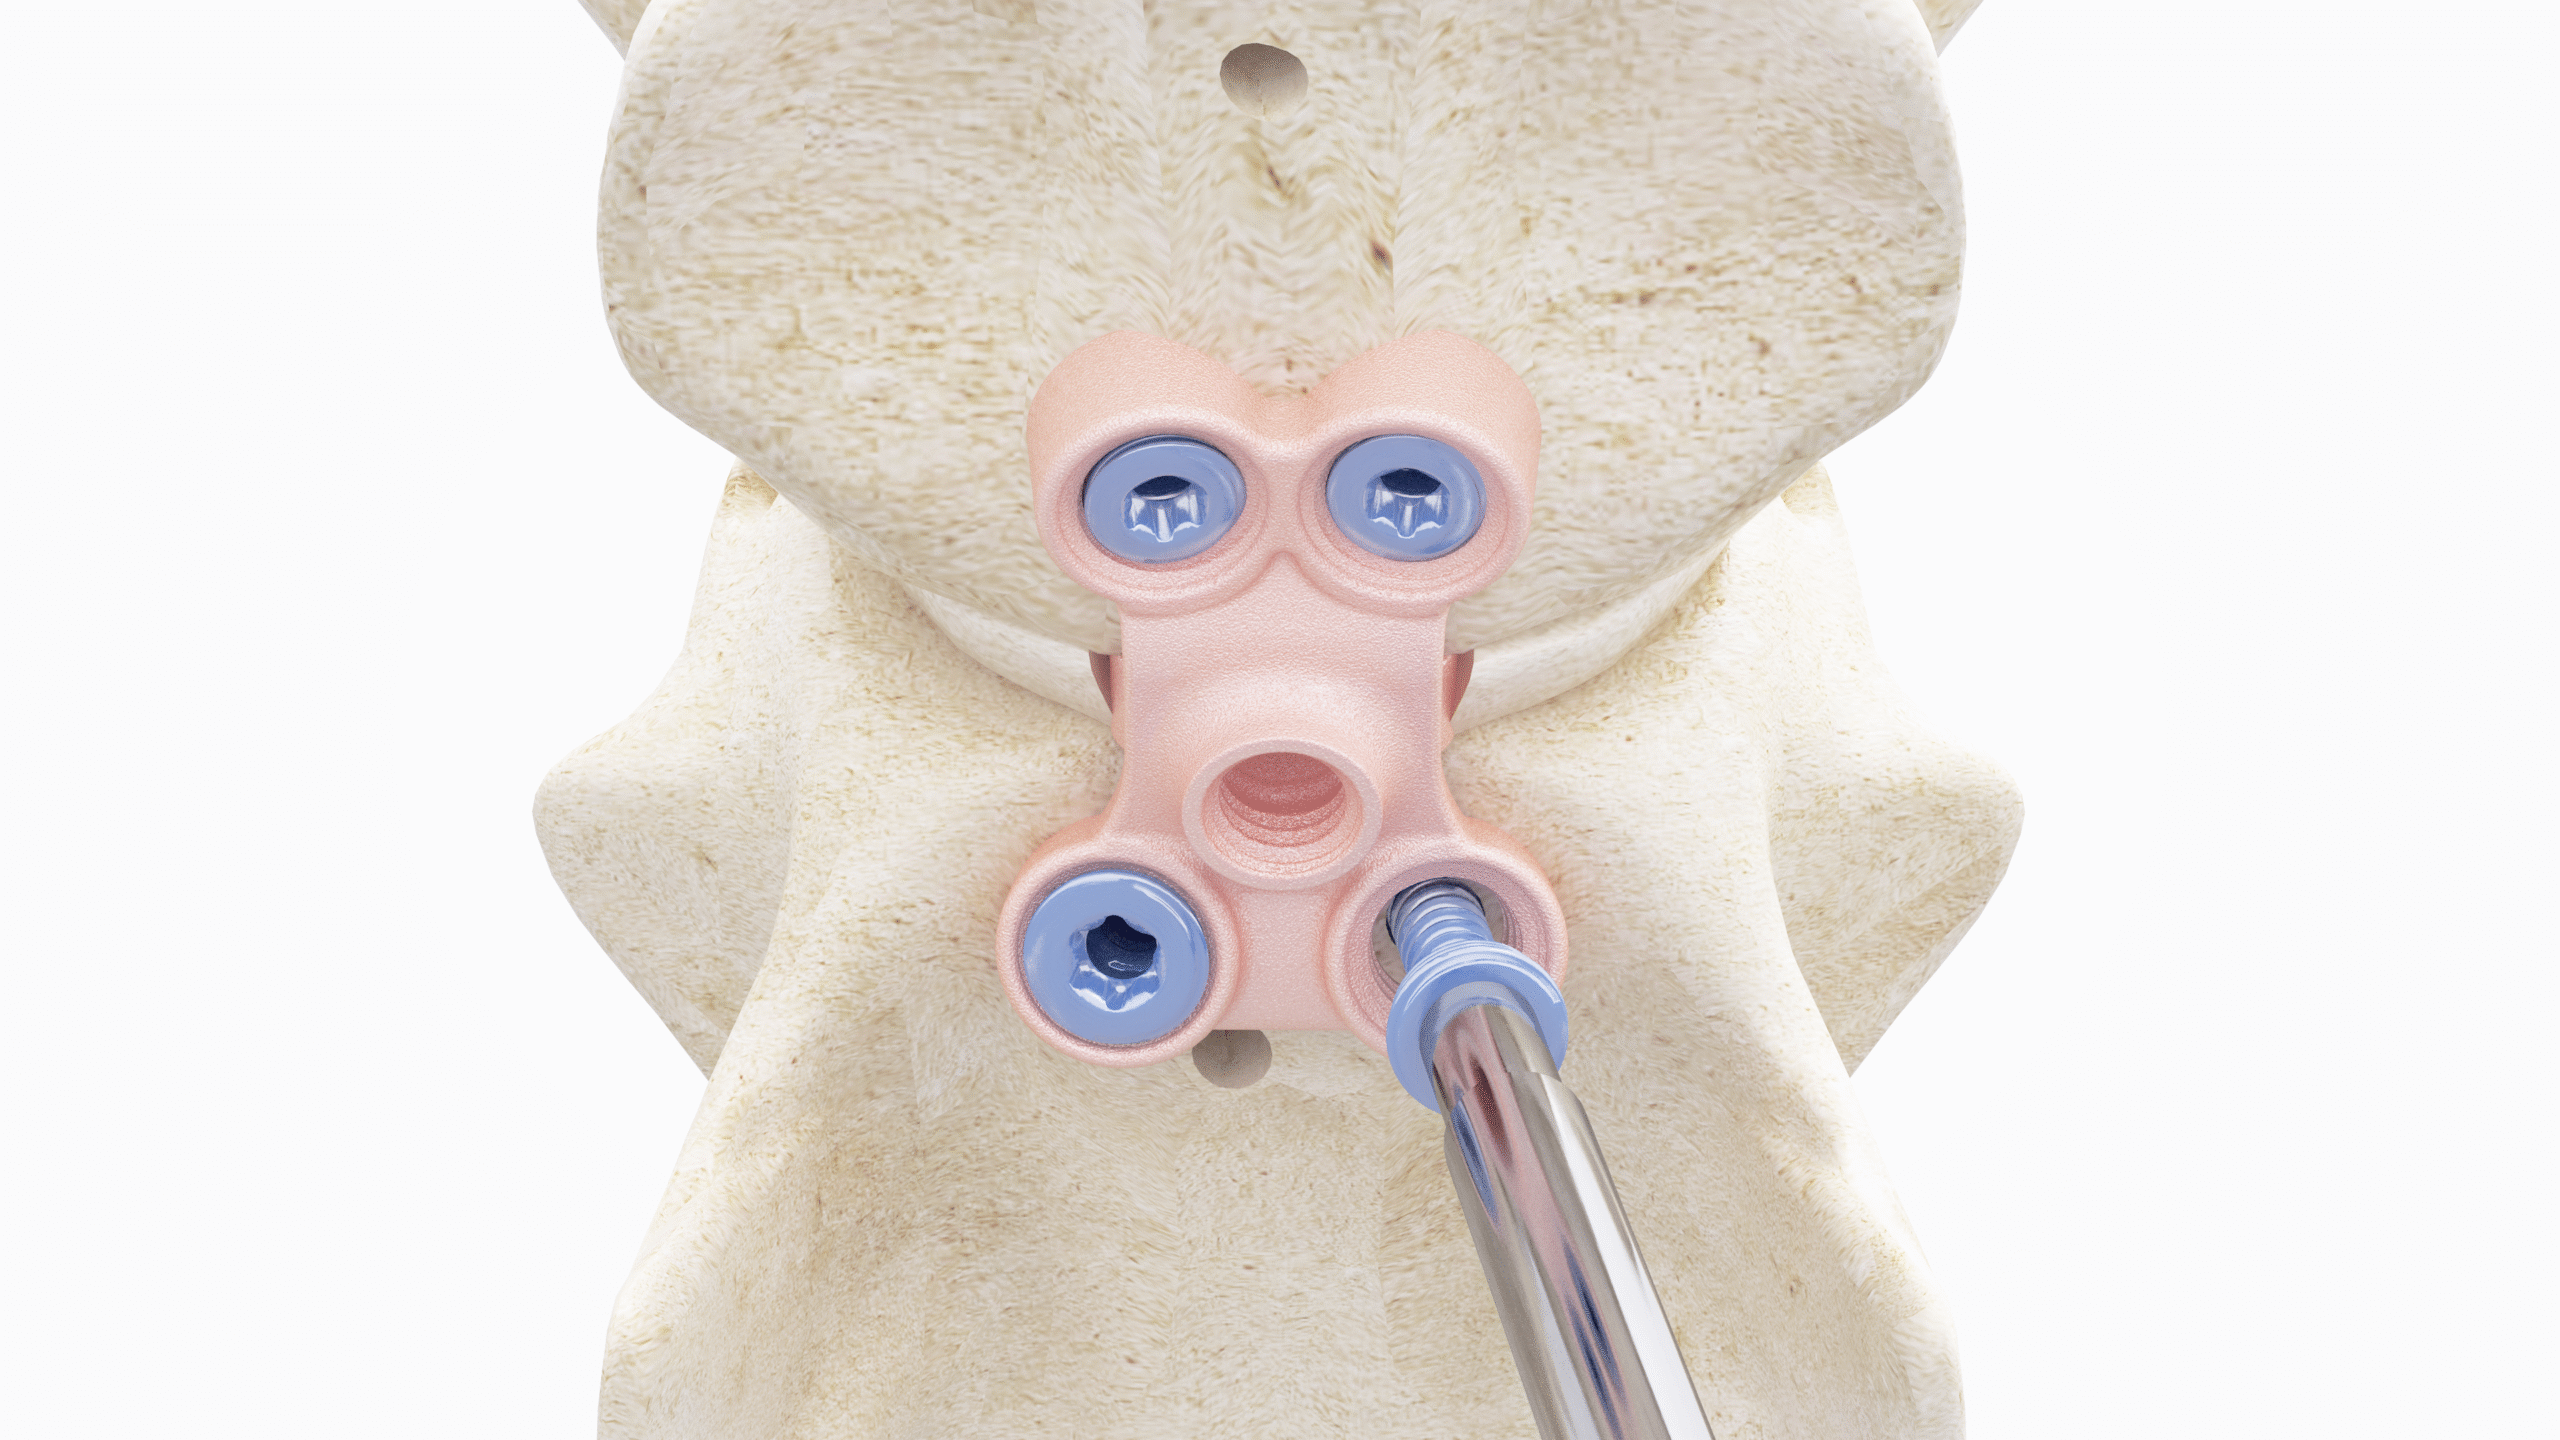

This course will explore the cannulated headless compression screw system, including its design, materials, and surgical applications. Participants will gain insights into the indications for these implants, such as elbow condylar fractures, ununited anconeal process (UAP), and hip procedures.

- Understand the design and function of the cannulated headless compression screw system, including its materials and biomechanical advantages.

- Demonstrate knowledge of anatomical approaches to the elbow and hip relevant to surgical fixation.